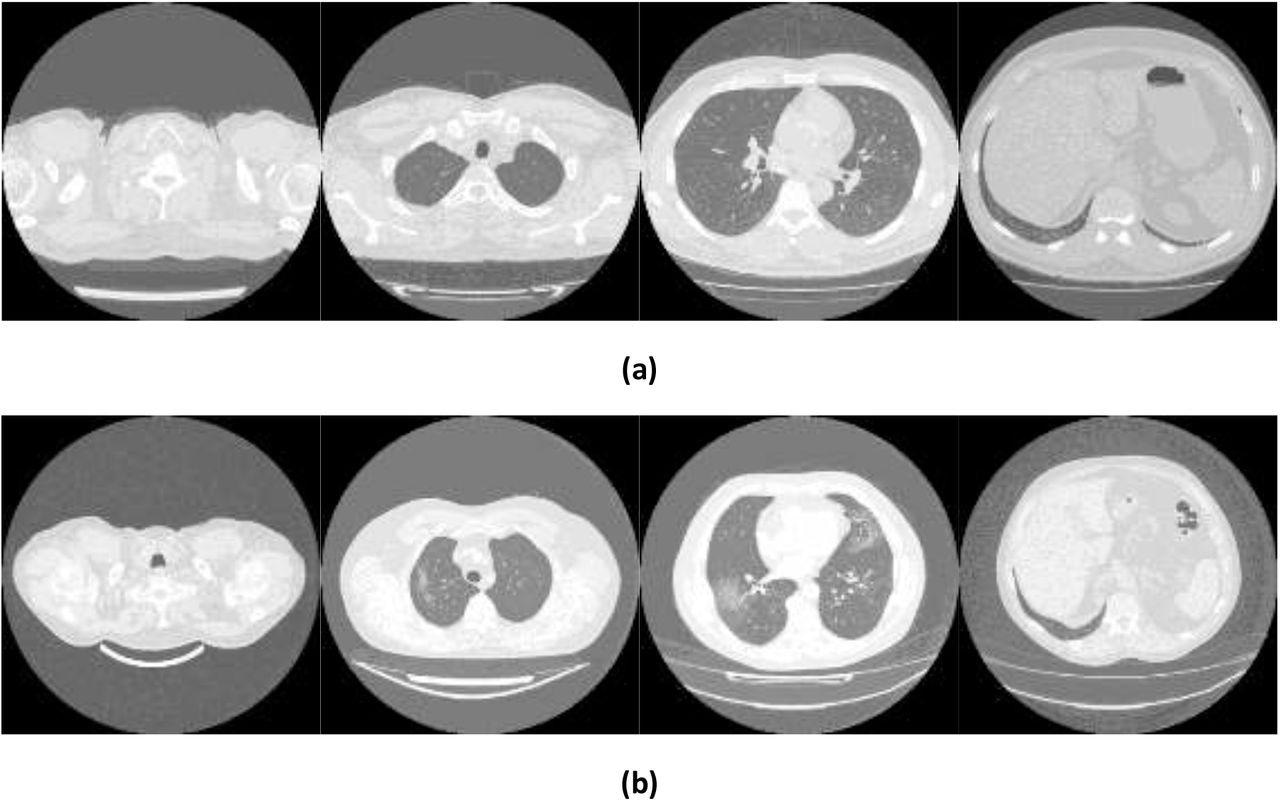

Example images showing (a) healthy and (b) COVID-19 lungs taken from the Mosmed dataset.